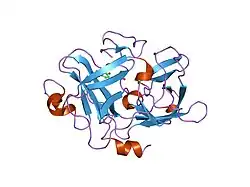

Urokinase is a 411-residue protein, consisting of three domains: the serine protease domain (consisting of residues 159–411), the kringle domain (consisting of residues 50-131), and the EGF-like domain (consisting of residues 1-49). The kringle domain and the serine protease domain are connected by an interdomain linker or connecting peptide (consisting of residues 132–158). Urokinase is synthesized as a zymogen form (prourokinase or single-chain urokinase), and is activated by proteolytic cleavage between Lys158 and Ile159. The two resulting chains are kept together by a disulfide bond between Cys148 and Cys279.[9]